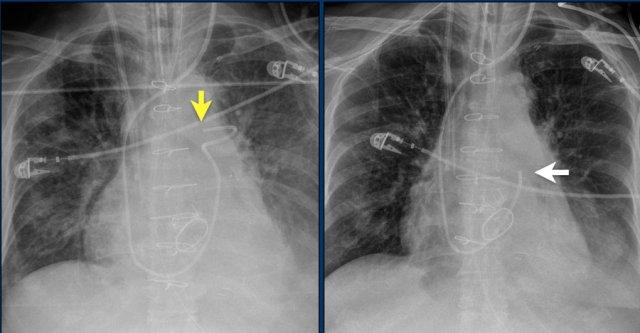

Hội chứng Twiddler

Hình ảnh bên trái cho thấy bệnh nhân có ICD được đặt đúng vị trí.

Vài tháng sau, thiết bị hoạt động không bình thường do hộp ICD và điện cực bị xoay (mũi tên vàng) và co rút lại (mũi tên trắng).